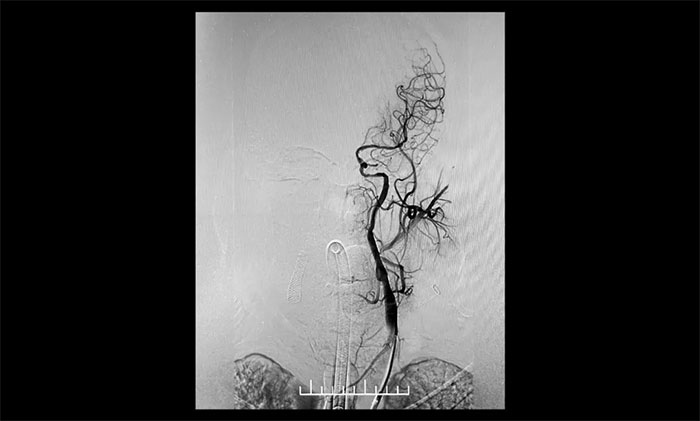

患者為老年男性,因言語不利,伴右側肢體活動不利入院。外院行頭顱CT檢查:雙側腦室旁及基底節(jié)區(qū)腔隙灶。入院后,頭顱MRI平掃+DWI+MRA提示,腦干、雙側小腦及雙側大腦半球多發(fā)腔梗、缺血灶;MRA:腦動脈硬化,左側頸內(nèi)動脈不完全閉塞,右側頸內(nèi)動脈C3-C6段、右側大腦中動脈M2段多發(fā)狹窄。“主動脈弓+全腦動脈造影”提示:右頸內(nèi)動脈起始段重度狹窄,左頸內(nèi)動脈起始段重度狹窄,串聯(lián)左頸內(nèi)動脈巖骨段中度狹窄,左頸內(nèi)動脈眼動脈段閉塞。

▲ 右頸內(nèi)動脈起始段重度狹窄